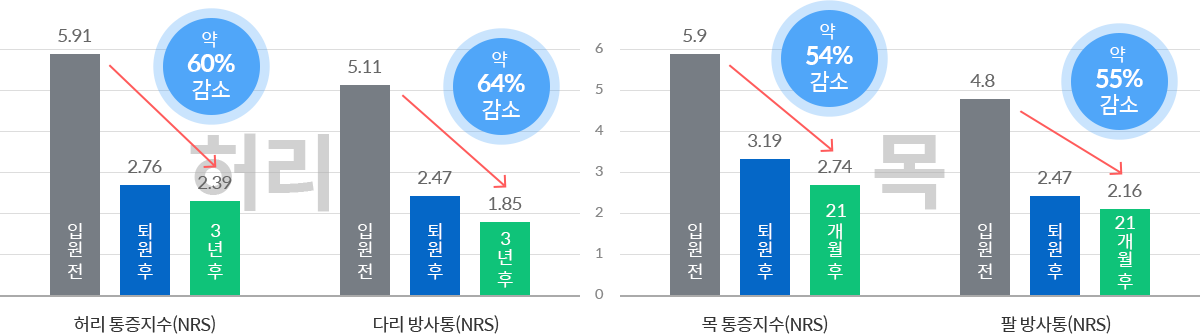

03퇴원 2~3년 후에도 치료효과 유지 및 호전

허리디스크

목디스크